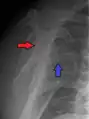

A diagnosis of shoulder dislocation is often suspected based on the person's history and physical examination. Radiographs are made to confirm the diagnosis. Most dislocations are apparent on radiographs showing incongruence of the glenohumeral joint. Posterior dislocations may be hard to detect on standard AP radiographs, but are more readily detected on other views. After reduction, radiographs are usually repeated to confirm successful reduction and to detect bone damage. After repeated shoulder dislocations, an MRI scan may be used to assess soft tissue damage. In regards to recurrent dislocations, the apprehension test (anterior instability) and sulcus sign (inferior instability) are useful methods for determining predisposition to future dislocation.

A Hill–Sachs lesion is an impaction of the head of the humerus left by the glenoid rim during dislocation.[6] Hill-Sachs deformities occur in 35–40% of anterior dislocations. They can be seen on a front-facing X-ray when the arm is in internal rotation.[11] Bankart lesions are disruptions of the glenoid labrum with or without an avulsion of bone fragment.[12]